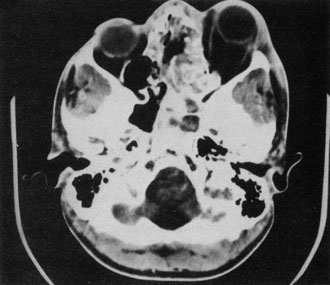

Rhinocerebral mucormycosis originates as a rhinitis, parapharyngitis, or sinusitis, and spreads by invasion of blood vessel walls, causing a necrotizing vasculitis with thrombosis of the vascular lumina and resultant infarction. The patient typically presents with unilateral orbital apex syndrome, including severe pain, visual loss, total ophthalmoplegia, corneal anesthesia, and multiple cranial nerve palsies.127 Orbital cellulitis presenting with early visual loss is one of the hallmarks of mucormycosis.72 Gangrene may occur of external periorbital tissues as well as of the hard palate and nose, and eschar-like crusting may be observed within the nose or on the hard palate (Fig. 23). Obstruction of the central retinal artery, ciliary arteries, and choroidal circulation can also be seen.124,125 Brain damage may occur because of spread of infection or infarction or occlusion of affected intracranial vessels.72

CT shows sinusitis with or without bone destruction and is indistinguishable from other causes of orbital cellulitis.128 MRI may show carotid narrowing, occlusion, and absent flow in the superior ophthalmic vein (Fig. 24).72

Fig. 24. Mucormycosis. A. A 72-year-old patient with acute myelogenous leukemia and invasive fungal sinusitis presented with orbital cellulitis. B. Involvement of hard palate with eschar. C. Fungi in the posterior ciliary artery.